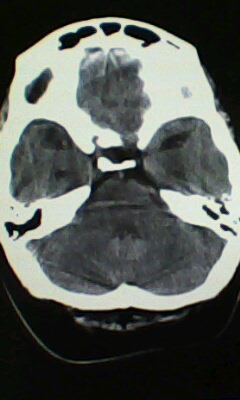

标题: CT25171:患者间断性头痛 无外伤史 [打印本页]

标题: CT25171:患者间断性头痛 无外伤史

脑穿通畸形

右侧额叶脑穿通畸形囊肿。

右侧额叶脑穿通畸形囊肿。支持!